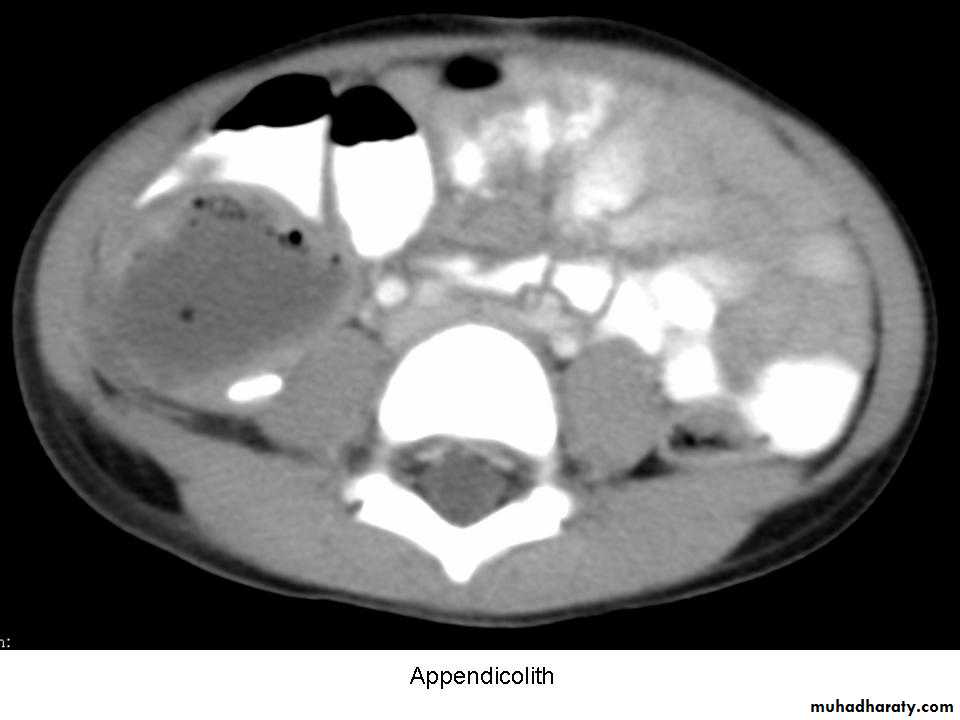

no single organism is responsible(mixed growth of aerobic and anaerobic organisms ).3- Obstruction of the appendix lumen

- Lymphoid hyperplasia

- faecolith (composed of inspissated faecal material,

calcium phosphates, bacteria and epithelial debris

- stricture

- faecolith obstruction of the appendix lumen